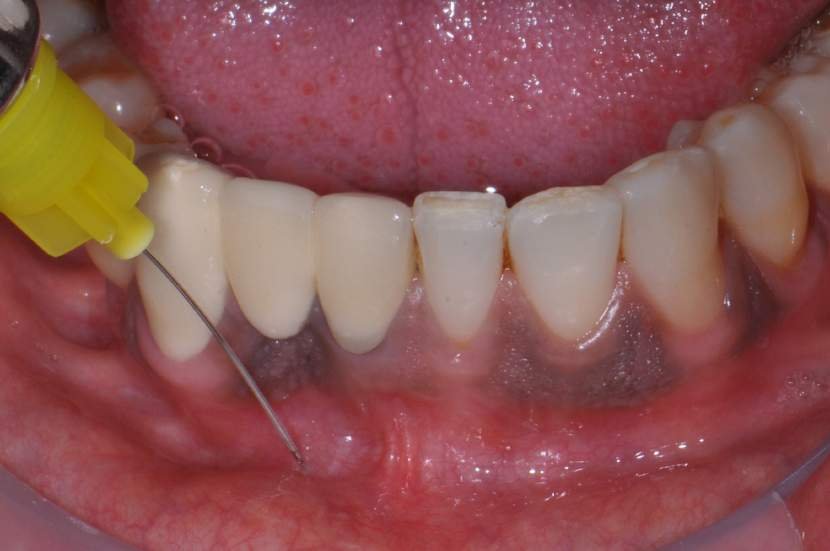

O procedimento cirúrgico para os implantes Slim segue um protocolo semelhante como outros implantes, porém muito simplificado. Normalmente utilizase a técnica anestésica infiltrativa. Um retalho mucoperiosteal deve ser rebatido para uma observação direta do rebordo ósseo disponível. No entanto, quando o tecido queratinizado e o volume ósseo abundantes estiverem presentes, uma cirurgia flapless é muitas vezes o protocolo cirúrgico de escolha.2

Para instalação de implantes de Ø 2.5mm é necessário apenas a utilização da fresa lança diâmetro de 2.0 mm. E para instalação de implantes de 3.0 mm utilização da fresa lança diâmetro de 2.0 mm e opcionalmente a fresa Countersink Slim 3.0mm (em casos de osso tipo I ou tipo II). O implante tem o ápice cortante e espiras que facilitam sua instalação. Os implantes Slim se apresentam de 1 em 1 mm de comprimento de 7 a 13 mm, o que facilita muito a escolha dos tamanhos no momento do planejamento.